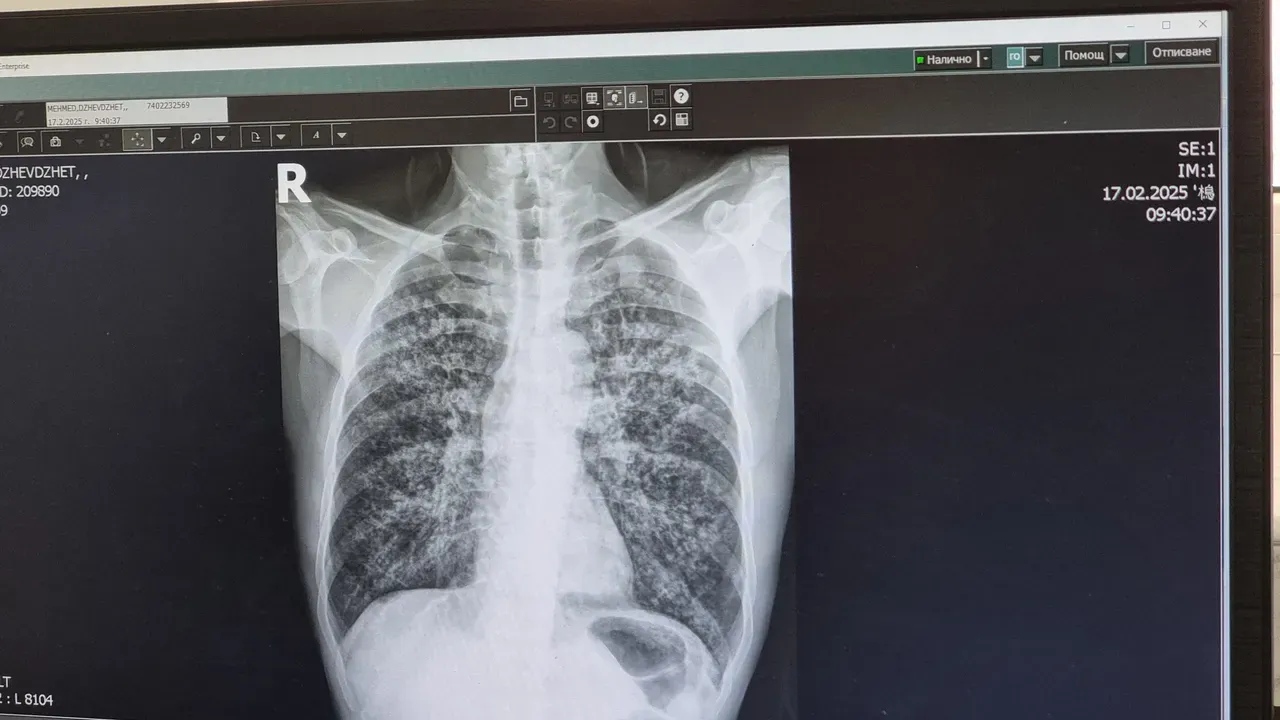

По повод Световния ден за борба с туберкулозата – 24 март, УМБАЛ „Свети Георги“ в Пловдив организира безплатни прегледи за туберкулоза.

Консултациите ще се провеждат в периода 23–27 март в Отделението по фтизиатрия към Клиниката по пневмология. Инициативата е насочена към ранното откриване на заболяването, което често протича без ясно изразени симптоми.

Туберкулозата остава сериозно, но лечимо заболяване при ранно откриване. Сред основните симптоми са продължителна кашлица, отпадналост, нощно изпотяване и повишена температура, но в част от случаите инфекцията протича без оплаквания.